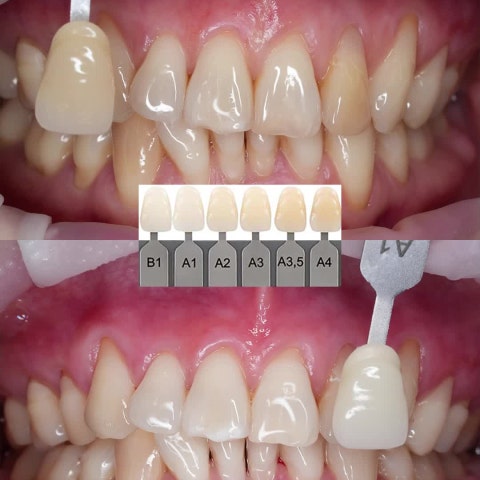

[슬라이드] 미백치료 전 미백제를 꼭 확인하세요. (20250731)

여름나기 다이어트만 하시나요? 치아미백도 같이 하세요! (20250721)